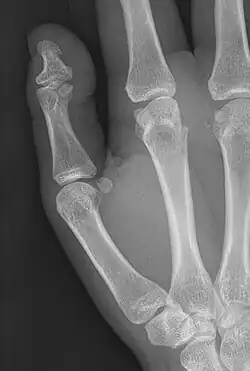

Brachyphalangy of the thumb's distal phalanx, also known as brachydactyly type D, with otherwise normal phalanges of the 2nd-5th digits | |

This condition is caused by either fusion or early closure of the phalange's growth plate. One example is brachydactyly type D, which is caused by an early closure of the thumb's distal phalange, leading to a congenitally short thumb with a similarly short and wide thumb nail.